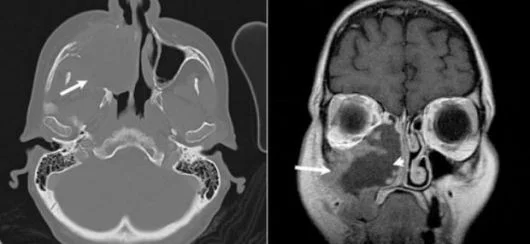

Il potenziale danno per la salute è dato dalla penetrazione e la deposizione nelle vie respiratorie delle particelle di legno prodotte nel corso del taglio e della lavorazione dei legnami e che con vari meccanismi, non ancora del tutto noti (allergici, meccanici e tossici) e spesso in associazione tra loro, provocano danni irreversibili all'organismo. Secondo la ricerca condotta dallo IARC (Agenzia Internazionale per la Ricerca sul Cancro), esistono sufficienti dati e informazioni per definire le polveri da legno cancerogene per l'uomo. I dati epidemiologici mostrano che l'esposizione a polveri di legno provoca tumori delle vie respiratorie superiori (naso e seni paranasali). Sono tumori rari, un caso su 100.000 persone, ma in alcune categorie di lavoratori, come quello del legno, l'incidenza è di 5-9 casi ogni 100.000 persone. L'esposizione a polvere di legno è responsabile anche di: